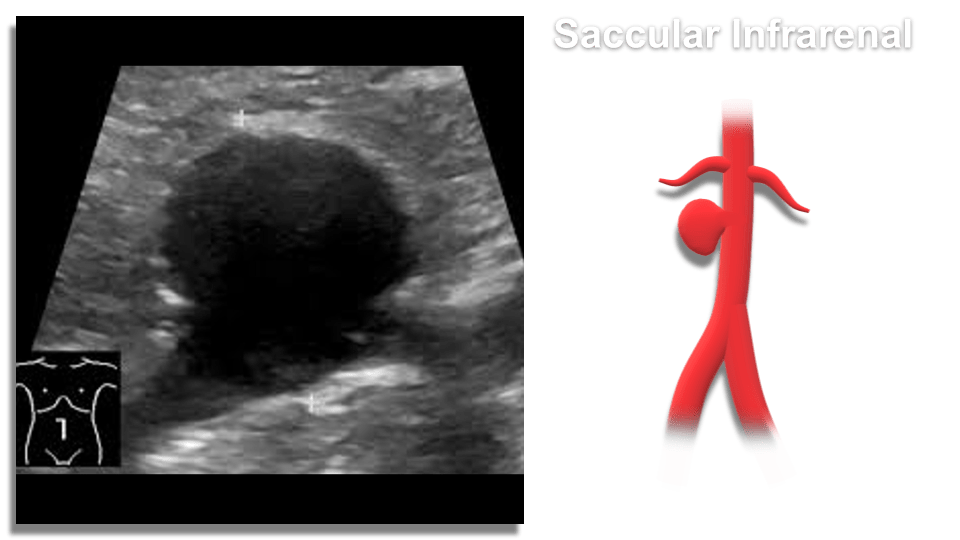

- Saccular – spherical in shape, appear like a pouch or sac from the vessel and are often filled with thrombus within the arterial wall (intramural)